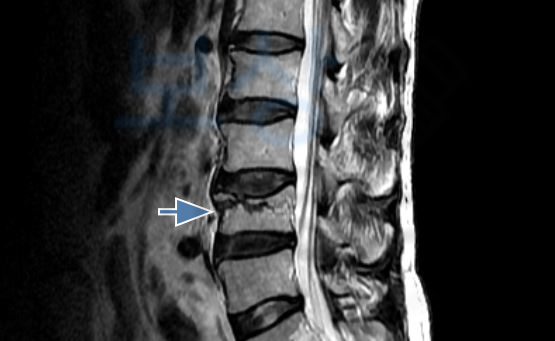

골절의 모습이 좋지않아 추후 큰 후유증을 야기할 수 있어 골시멘트술을 받으셨는데요, 조@@님께서 받은 시술은

골절된 척추체를 목표로

의료용 시멘트를 주사하는

척추의 안정성을 위한 시술입니다. 골시멘트시술을 받은 이후